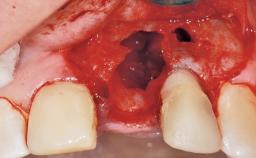

A 30-year-old female patient had lost tooth 21 and was referred to our clinic for consultation and treatment. Due to advanced apical infection, tooth 21 had been extracted two months earlier at another clinic and an acrylic-resin tooth had been bonded to the adjacent teeth. The patient desired implant treatment to avoid any damage to the adjacent natural teeth. While the patient had no history of any systemic disorder, she was a heavy smoker and exhibited medium to advanced periodontitis in the entire jaw. After the initial treatment to achieve a pocket probing depth of less than 4 mm and no bleeding on probing, a decrease in the height of the papillae mesial and distal to the extraction site and overall gingival recession were observed.

Soft Tissue Anatomy Intact Defective

Bone Volume Horizontally and vertically sufficient Horizontally deficient Deficient vertically or deficient vertically AND horizontally